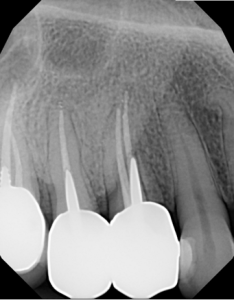

This video demonstrates a fully guided immediate implant placement protocol following premolar extraction, combined with immediate provisional restoration. The case highlights a digitally driven workflow designed to enhance accuracy, efficiency, and prosthetically guided implant positioning.

Step-by-step, the procedure covers atraumatic tooth extraction, guided implant placement using a surgical guide, and chairside fabrication and delivery of an immediate provisional restoration. Clinical considerations for achieving primary stability, soft tissue preservation, and optimal emergence profile are emphasized to support predictable esthetic and functional outcomes.